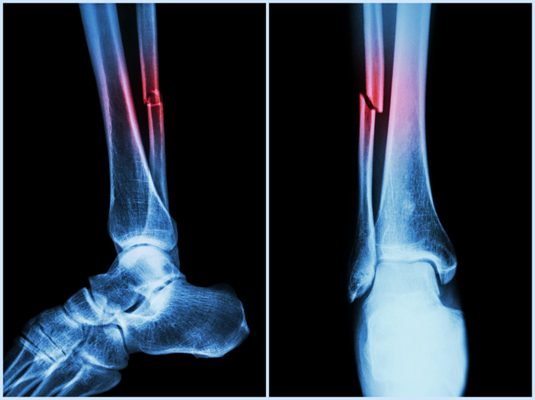

骨折圖片